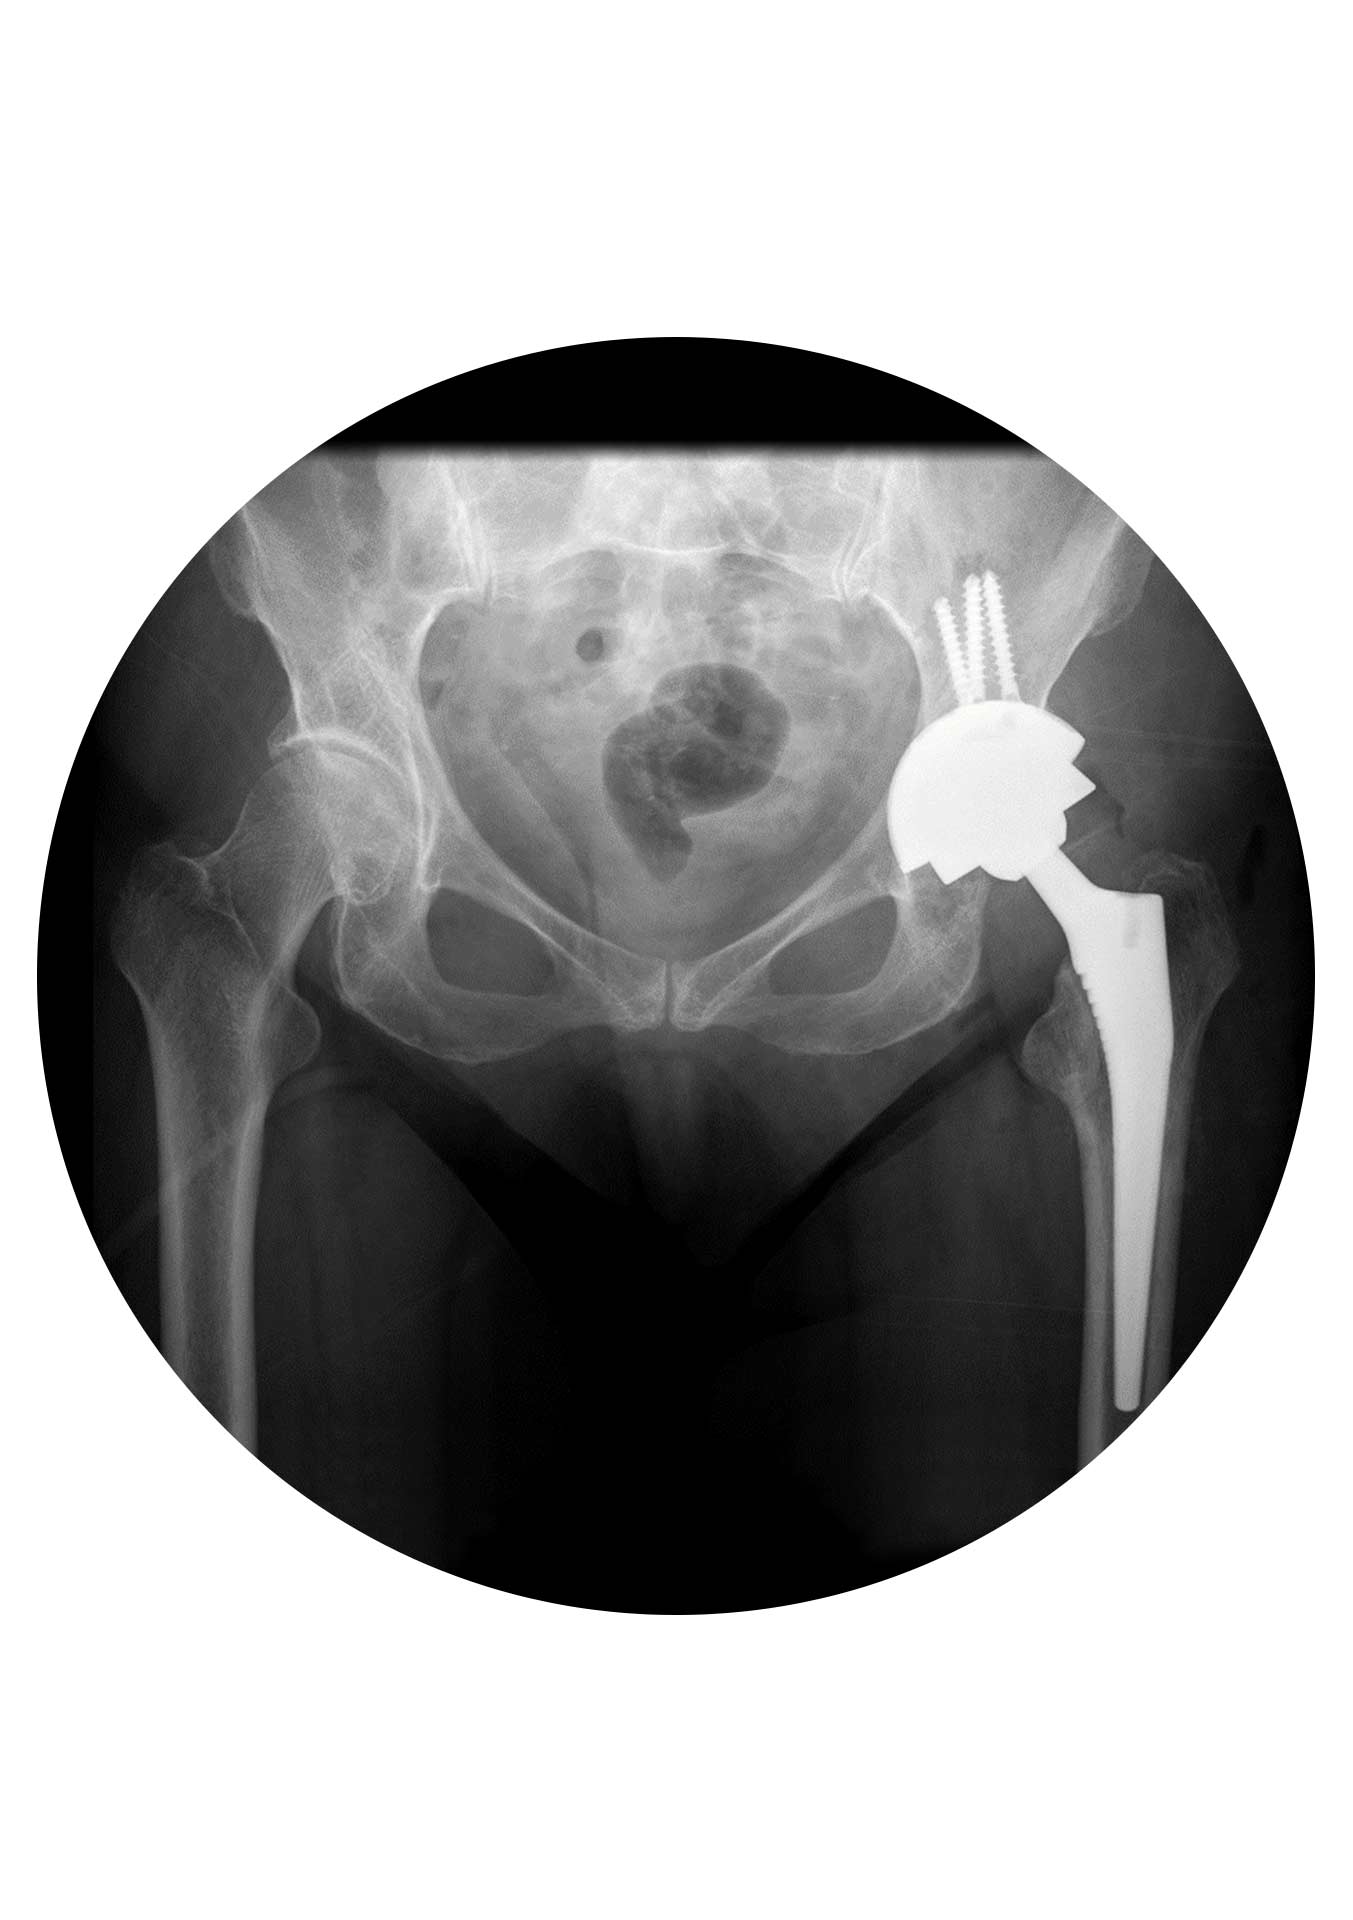

Segundo: reconstrução da “nova” articulação. Embora o momento da remoção dos implantes seja importante no resultado da cirurgia de revisão, esta é na sua essência uma cirurgia de reconstrução.

Em relação ao material disponível (ao contrário da prótese primária) ele é extremamente variado e complexo… dividindo-se de uma forma simplista em material de reconstrução acetabular (redes, cages, cups multi-furos, aumentos e batentes) e material de reconstrução femoral (hastes modulares, hastes tipo Wagner, hastes com fixação distal, placas trocantéricas e cabos de aço)… até material customizado (implantes produzidos especificamente para cada caso).